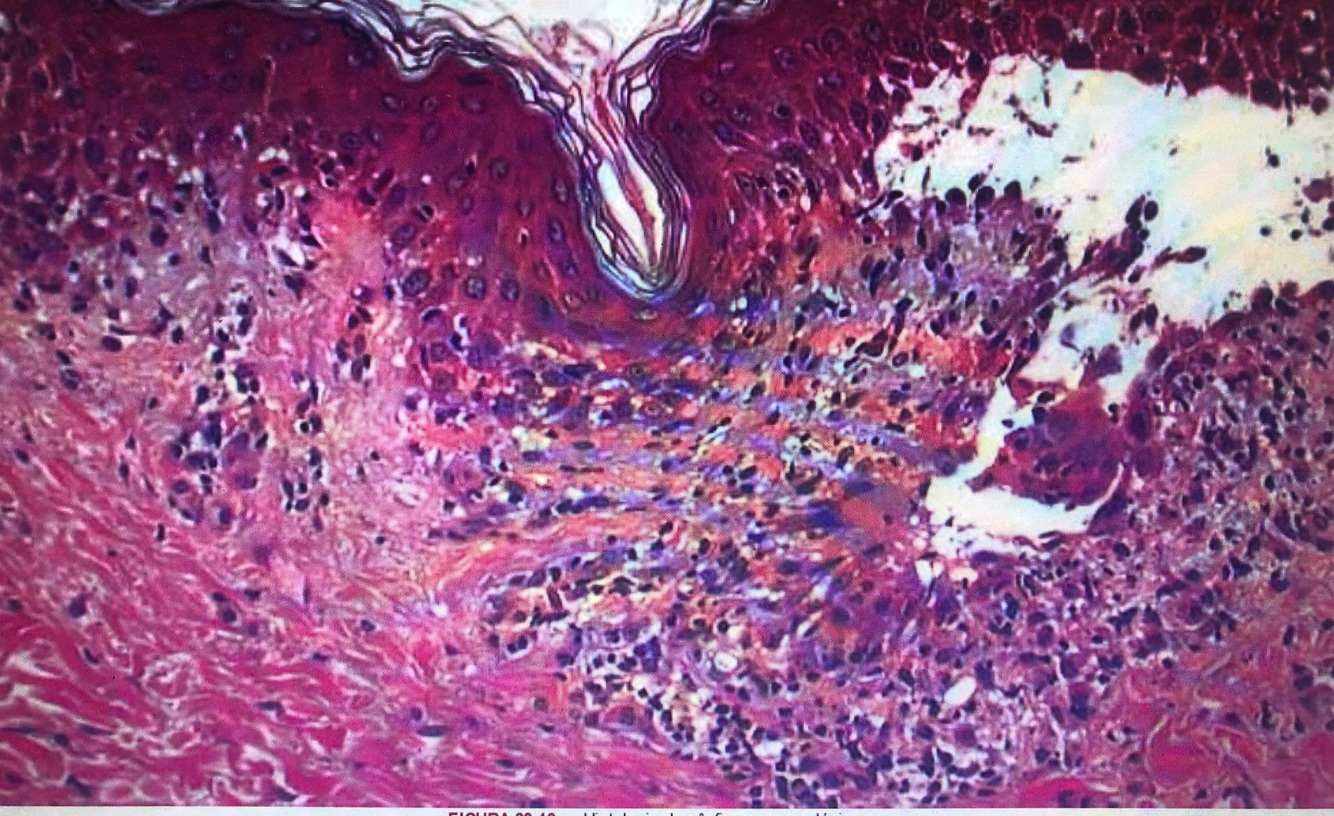

Qual diagnostico?

PF (acantolise, clivagem epidermica alta)